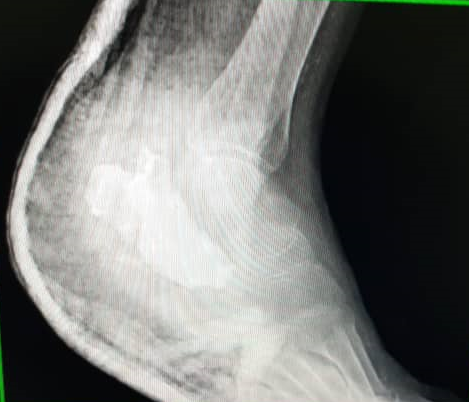

On 01-21-2021 the patient is taken to the operating room, and a new sample is taken for biopsy and culture, apart from surgical cleaning and filling with polymethylmethacrylate (bone cement) prepared with antibiotics (gentamycin). Additionally, he started antituberculosis specific treatment with a satisfactory response after a short while, recovering mobility with no pain and diminution of the local swelling. After two months of treatment the patient died due to complications related to his disease.

The image studies performed in a serial way, allow to observe the osteolytic process and the inflammatory response seen in those chronic cases. MRI, is especially useful in evaluating soft tissues, and the computed tomography, very much useful in evaluating bone destruction, worked together in these cases. It should be advice, the use of the bone scan, or PET-CT or virtual-PET, to discard polyarticular affectation. This entity is very often confused with other pathologies. Differential diagnosis has to be made with osteomyelitis, Paget’s disease, sarcomas and other pseudo tumoral lesions, which usually are the initial diagnosis, and TBC is a discard diagnosis. The adequate diagnosis is made late because of lack of pathognomonic findings (Figure 1 - 4).10

Figure 4 Post-op x-ray 01-22-2021.